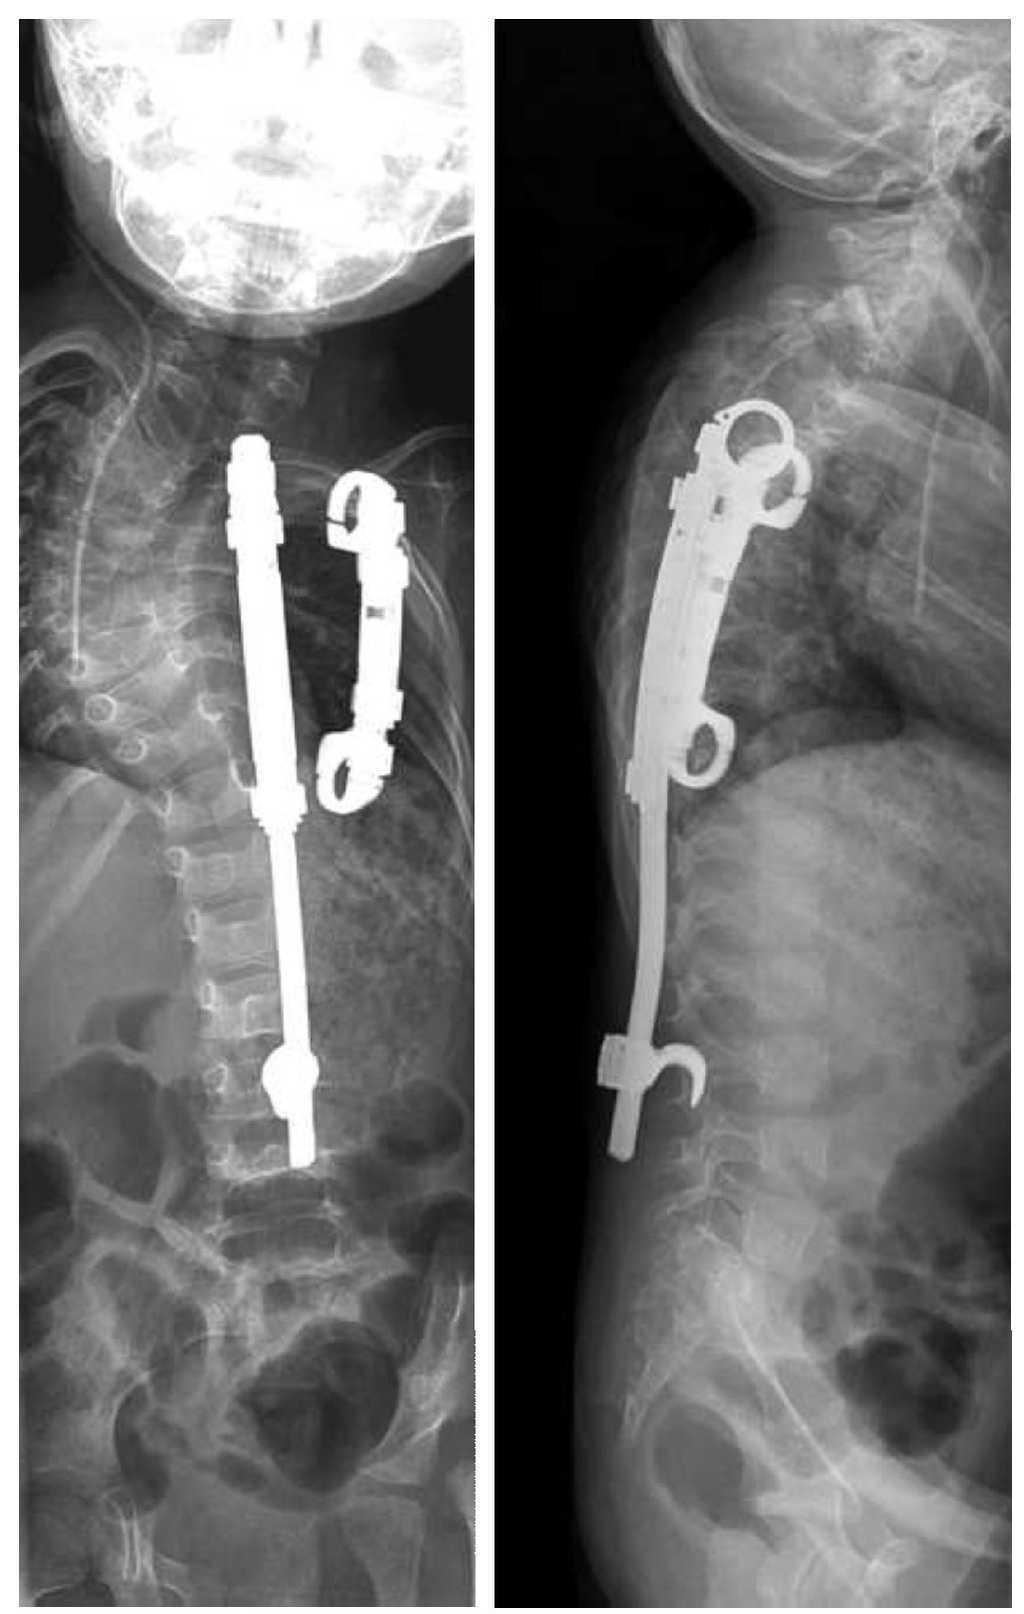

La indicación para la intervención fue en 16 casos una escoliosis congénita (figs. 24a-24c), en once casos una escoliosis neurológica y en doce casos una EIP. Las curvas se determinaron según Cobb. El ángulo de Cobb antes de la intervención medía un promedio de 65º (45-130º), y después de la intervención, un promedio de 32º (25-75º). En 18 pacientes tratamos una escoliosis torácica, en 18 pacientes una toracolumbar y en tres pacientes una lumbar (mielomeningocele). En 18 casos se utilizó un implante «costilla a costilla», en cinco casos un sistema de barra doble hasta la pelvis y en 18 casos un sistema híbrido (figs. 25 y 26).

Figuras 26a y 26b. a) Radiografía postoperatoria en proyección anteroposterior después de corregir una escoliosis congénita mediante la técnica híbrida. b) Radiografía lateral postoperatoria.